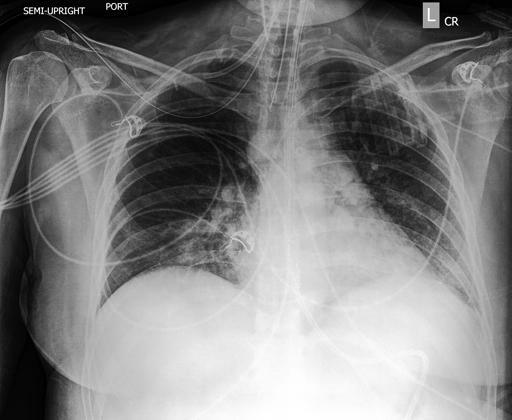

Chest X-rays may be divided into three principal types, according to the position and orientation of the patient relative to the X-ray source and detector panel: posteroanterior, anteroposterior, lateral. The posteroanterior (PA) and anteroposterior (AP) views are both considered as frontal, with the X-ray source positioned to the rear or front of the patient respectively. The AP image is typically acquired from patients in the supine position, while the patient is usually standing erect for the PA image acquisition. The lateral image is usually acquired in combination with a PA image, and projects the X-ray from one side of the patient to the other, typically from right to left. Examples of these image types are depicted in Figure 1.

Figure 1: Left: posterior-anterior (PA) view frontal chest radiograph. Middle: lateral chest radiograph. Right: Anterior-posterior (AP) view chest radiograph. All three CXRs are taken from the CheXpert dataset [131], patient 184.